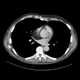

Pericardial lipoma